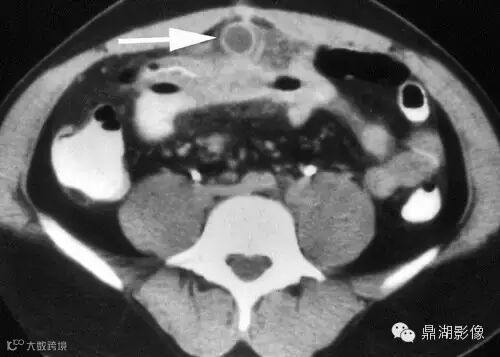

22岁男性,发热,大便潜血试验阳性,脐部下方见管状结构并环形强化(箭),周围可见炎性改变,邻近小肠壁增厚。